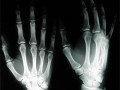

На первое место британцы поместили открытие рентгеновского излучения и изобретение использующих его медицинских приборов. Этот вариант поддержали 10 тысяч опрошенных. Второе место заняло открытие пенициллина. На третье место жители Великобритании поместили определение структуры ДНК. Далее следуют создание корабля "Аполлон-10" и баллистической ракеты "Фау-2", изобретение паровоза, вычислительных машин, парового двигателя, массового автомобиля и телеграфа. Исходный список изобретений был составлен сотрудниками Музея науки.